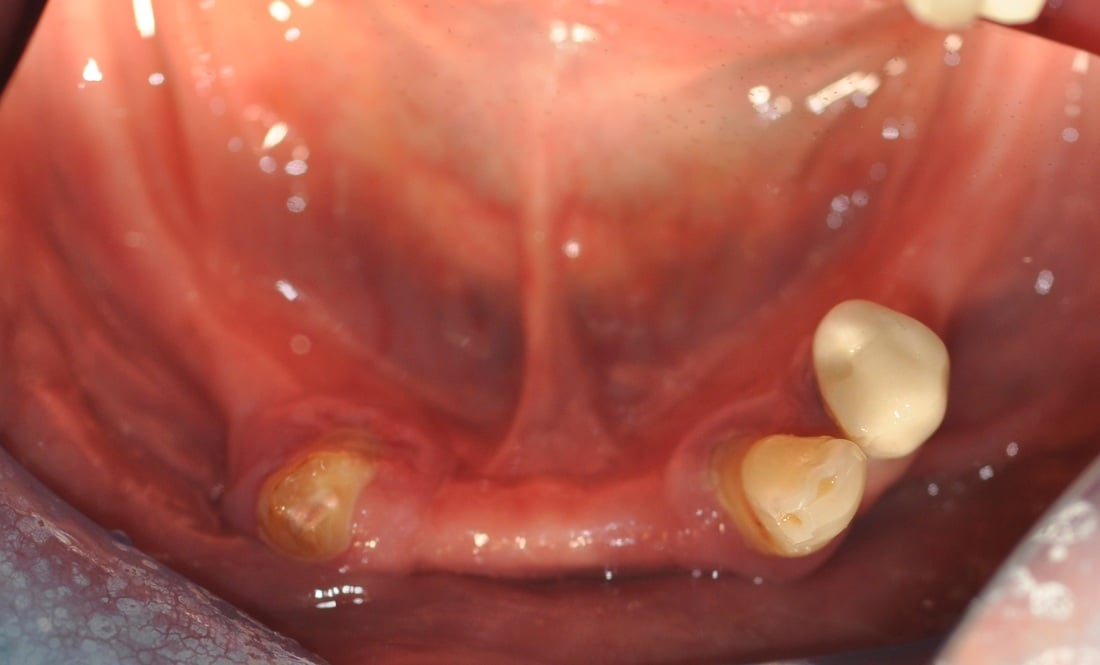

This 65 year old man had pain in his lower jaw, during initial emergency exam after recent extraction of the lower left molar done with another dentist.

The patient suffers from Type 2 insulin-dependent diabetes. For unknown reason, the extraction site had not been closed with sutures by his previous dentist. On the second day after extraction, a “dry socket” had developed. This infection had caused moderate loss of bone due to the inflammatory process.

The treatment performed by Dr, Andrews included :

- Management of the dry socket.

- Simultaneous placement of three dental implants, combined with bone graft.

- PRF protocol was also used, in order to decrease the likelihood of complications (infection, bleeding), to accelerate the healing process and to decrease post-operative discomfort.

All three implants were successfully integrated and restored 6 months after the surgery.